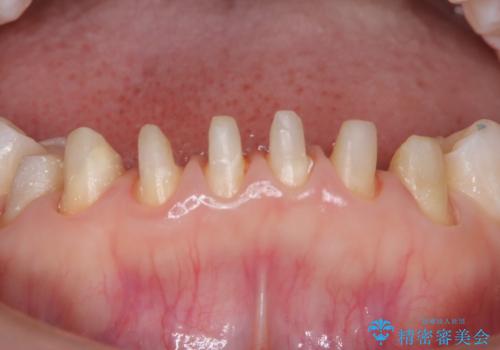

【オールセラミック】下の前歯が痛い。

- 以前に治療した前歯が痛むことを主訴に来院されました。

根っこに病気があり、根管治療から被せ物まで治療を行いました。

根管治療を行った後、3ヶ月間治癒の確認をしてからオールセラミックスペシャルで治療を行いました。